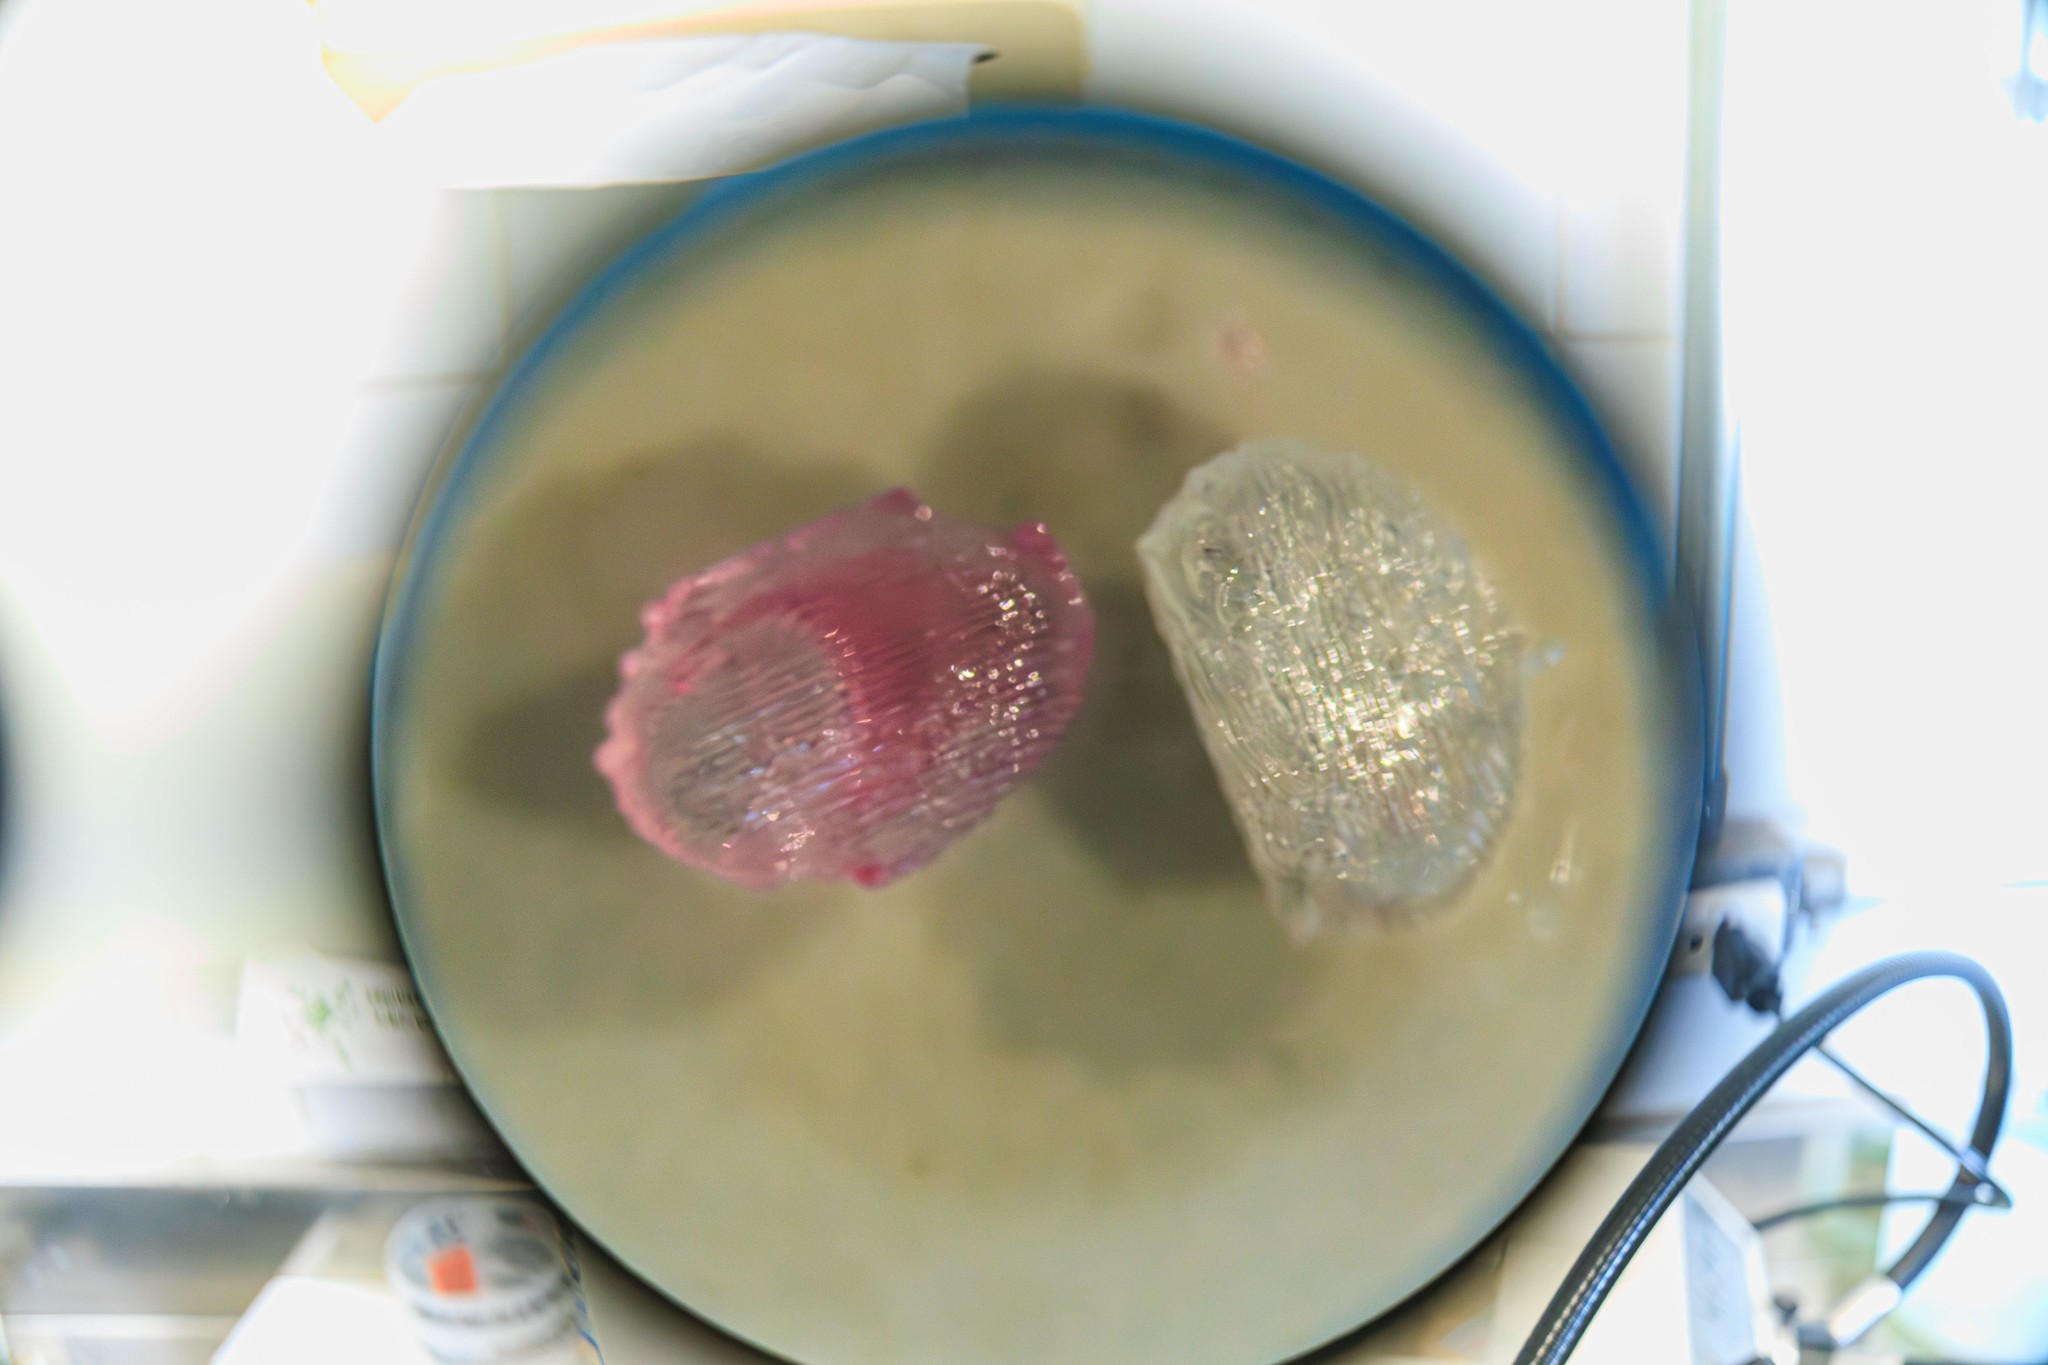

Dispositivo 3D imita ambiente da medula óssea em laboratório

Igor Alisson/Inova Unicamp

A partir daí, desenvolveram o dispositivo em 3D, feito de um material compatível com o corpo humano. Ele funciona como uma estrutura onde as células ficam organizadas e conseguem se manter vivas e funcionando.